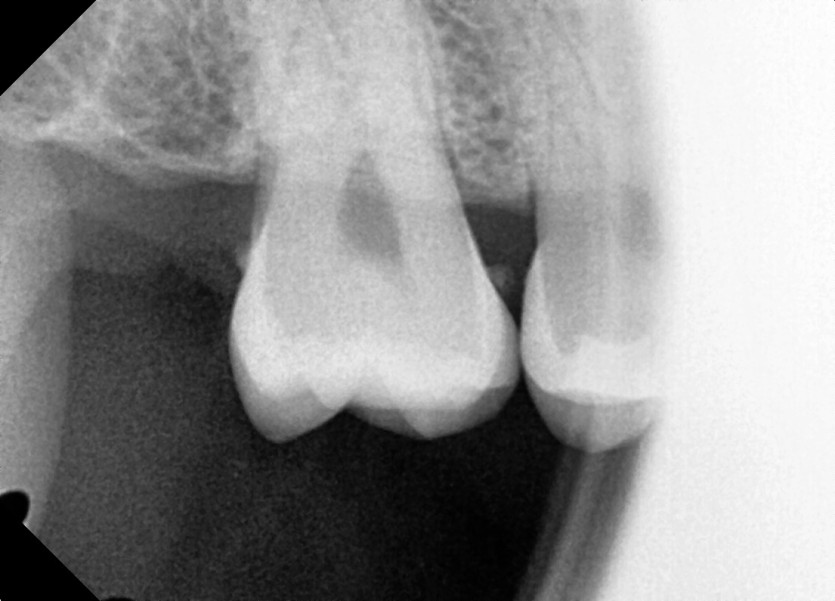

#18,48 사랑니 발치

구강 외과 전문의가 당일 발치했습니다.